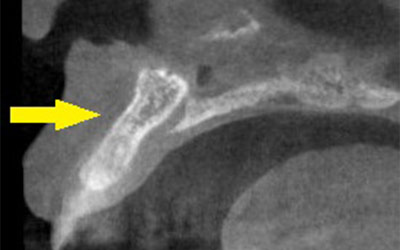

この患者様は、上顎の右前歯が差し歯になっていたのですが、歯の根の先の部分が、腫れを繰り返し、歯根の破折も考えられるとのことで、抜歯して、インプラントかブリッジかと説明されたそうで、インプラント治療を希望されて、当院に相談に来られました。

CTでみると、歯の根の外側の薄い骨がなく、ここに炎症を起こすと、症状の改善は難しい状態でした。抜歯してインプラントということで了承され、抜歯即時インプラント埋入も考えられたのですが、歯の根の状態、骨の状態を考えて、抜歯して、治癒を待ってインプラント埋入をすることとしました。

抜歯して5か月経過後にCT撮影すると、非常に良く治癒していましたが、骨の厚みが4mm程しかありませんでした。そこで、インプラント埋入と同時に外側に人工骨と自家骨を混合して補填し、人工の膜(メンブレン)で覆うという、骨の厚みを造成する手術(GBR)を併用しました。

手術後のCTです。うまくインプラント埋入、骨造成ができていると思います。